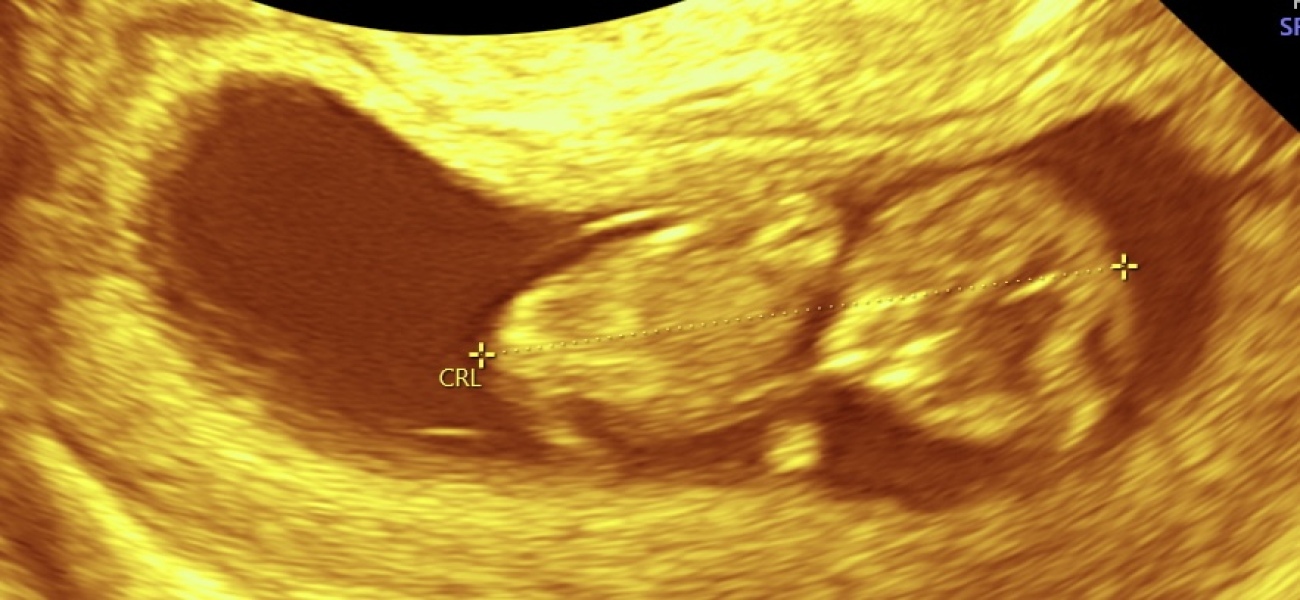

AppleTree16 · 23/03/2024 18:19

We also had a scan today. Measuring slightly ahead so now 10+6 not 10+3 as we thought. Baby bouncing all over the screen!

We also saw the mouth moving today. So amazing to see at such an early point. ❤️